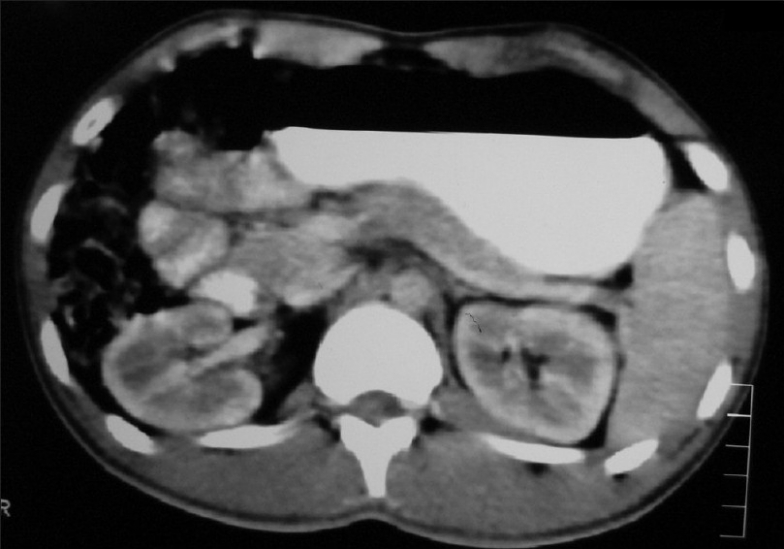

Contrast enhanced Computed tomography (CECT) abdomen showed extrinsic compression of liver by subpleural metastases with multiple para-aortic and peri-aortic lymphadenopathies [Figure 8]. USG (Ultrasonogram) of scrotum was normal. His serum tumor markers were alpha fetoprotein: 4.3 ng/mL beta human chorionic gonadotropin: 39.4 mIU/mL lactate dehydrogenase: 742 U/L.

| Figure 8 CT abdomen (2007) shows multiple para aortic lymphadenopathy

| Figure 11 CT abdomen (2008) shows reduction of para aortic lymphnodes to sub centimeter size after chemo